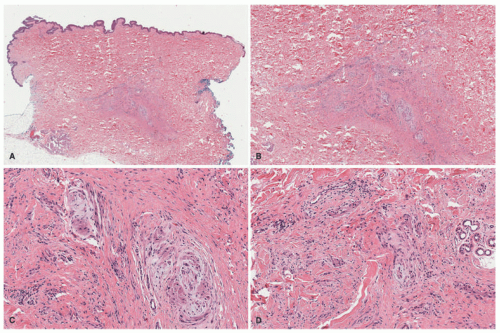

The histopathologic features of DF are relatively uniform in the majority of cases as a dermal-based spindle cell proliferation positioned in the mid-dermis, situated beneath the flattened epidermis or pushing into the underlying subcutis with absent or minimal infiltration into the subcutis, unlike the DFSP (Figure 24-31A-C). The lateral dermal borders typically demonstrate the spindle cells extending into the collagen with so-called collagen trapping. Within the body of the lesion, the spindle cells are arranged in short storiform or fascicular profiles. Some nuclear pleomorphism may be present together with scattered mitotic figures. Lymphocytes and even eosinophils may be identified in the background. Variant patterns include those with blood-filled nonvascular spaces (aneurysmal DF), numerous macrophages with hemosiderin-laden cytoplasm, and xanthomatized macrophages. Touton giant cells in the latter setting presents the microscopic dilemma and distinction (if there is one) from the xanthogranuloma (Figure 24-32). More than one histologic pattern is present in a minority of DFs.141

FIGURE 24-31. A-C, Dermatofibroma presenting on the breast of a 17-year-old female. A, The spindle cell tumor is centered in the dermis as a circumscribed nodule. Mild acanthosis noted in the overlying epidermis. B, This focus shows the uniform spindle cells arranged in a storiform profile. C, The periphery demonstrates the insinuation of spindle cells into adjacent dermis with collagen trapping. Note the limited extension.

Cellular variant of DF (cellular benign fibrous histiocytoma) is recognized by its relatively monotonous spindle cell composition and its fascicular architecture. These tumors are more mitotically active than the common DF, and focal necrosis may be present.142 Extension into subcutis is a frequent finding and infrequently like the common DF may be centered in the subcutis.

It is unnecessary in most DFs to apply immunohistochemistry, but like the DFSP, these tumors are CD34+; the CD34 staining is usually localized to the periphery unlike the diffuse staining in DFSP (Figure 24-33). Unlike the DFSP, DF and its variants are diffusely reactive for CD163 in addition to factor XIIIa (Figure 24-33).143 Cellular DF or cellular benign fibrous histiocytoma may be diffusely positive for CD34 in some cases, but desmin reactivity is present in the latter tumor in contrast to DFSP.144

The atypical variants of DF encompass a heterogeneous group of lesions that are characterized by a large size (>2 cm), more infiltrative borders, extension into the adipose tissue, frequent (>5 per 10 HPFs) or atypical mitoses, and extensive areas of necrosis.145 Nonetheless, most of the lesions are characterized by areas of conventional DF. Within this group, the rate of local recurrence is higher (˜15%) and on rare occasions metastases can be present. Horenstein et al also introduced the concept of “indeterminate fibrohistiocytic lesions” to highlight a group of neoplasms with a small size (<2.0 cm), low mitotic index (<4/10 HPF), a keloidal collagen pattern, a slight degree of pleomorphism, but honeycomb and deep infiltration into the adipose tissue. These lesions were partially immunoreactive for factor XIIIa and CD34.145,146 This tumor type is seen in children.147

FIGURE 24-32. A-D, Dermatofibroma versus juvenile xanthogranuloma. Fibrohistiocytic lesion with epidermal induction changes (A). Collagen trapping at the periphery is seen (B). Xanthomatized cells (C) and Touton-type giant cells (D) are seen. Digital slides courtesy of Path Presenter.com.